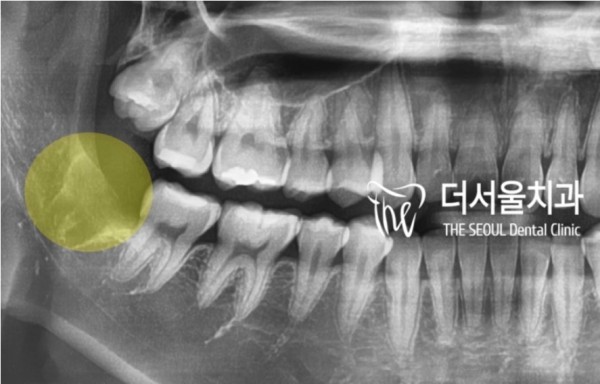

저희 태평역치과 더서울치과에서 엑스레이를 통해

진료를 해 본 결과 신경관과 가깝게 위치한 사랑니의 뿌리가

확인되고 있었습니다.

Taepyeong Station Dental Clinic The Seoul Dental Clinic has an X-ray

The root of the wisdom tooth, which is located close to the nerve tube

It was being checked.

꽤 고난이도의 수술이 필요한 상황입니다.

저희 더서울치과의 CT 촬영으로 더욱 자세히 관찰을 한 결과

다행히 약 2mm의 거리가 있어 문제없이 발치를 할 수 있었습니다.